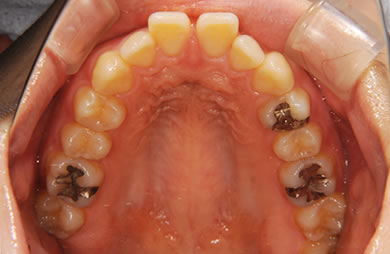

| 性別/年齢 | 女性 / 24歳 | ||||||||||||||||||||||||||||||||

| 主訴 | 矯正治療を希望し治療方針を相談する為、来院。 | ||||||||||||||||||||||||||||||||

| 治療方針 | 舌が横にはみでて、上下の歯が全く咬んでいない状態です。口元はきれいなので、歯は抜かずに歯列を少し横に広げて並べます。ゴムを使用したり、舌を訓練したりとても協力が必要な症例です。 | ||||||||||||||||||||||||||||||||

| 治療内容 | 唇側矯正(ホワイト)、保定装置 | ||||||||||||||||||||||||||||||||

| 総治療費 | 721,000円 | ||||||||||||||||||||||||||||||||

| 治療期間 | 9ヶ月 |